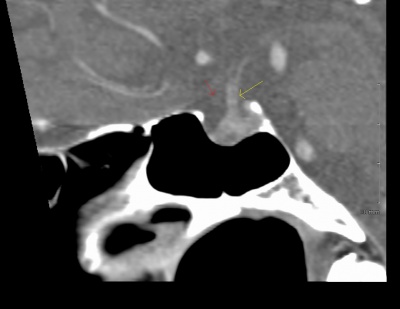

71 year old man with ~10 diopters of myopia OU and tilted optic nerves on clinical exam. Goldmann visual field testing shows bilateral superotemporal defects. CT sella shows no chiasmal lesion.